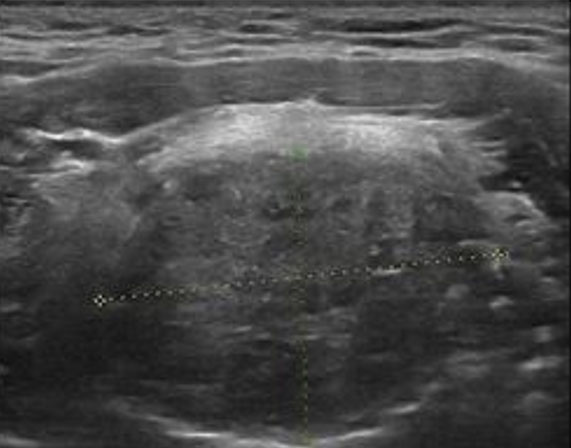

The Tc99 scan investigation (TC99M *I, 72 MBq, i.v.) highlighted increased tracer uptake consistently with the structure reported on ultrasound imaging. Uptake in the anterior region of the neck and in other areas of the body was absent (Figure 3).

Figure 3: Scintigraphy scan of the lesion (TC99M *I, 72 MBq, i.v.).